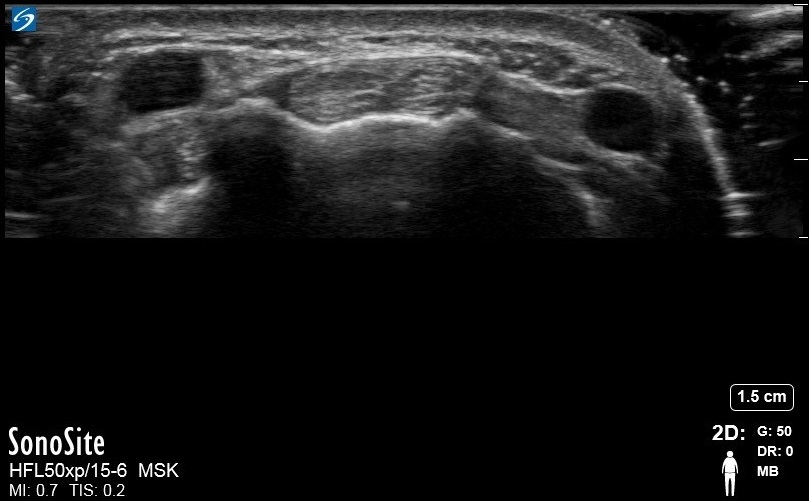

Wrist Extensor Carpi Radialis Brevis and Extensor Carpi Radialis Longus 3 Image